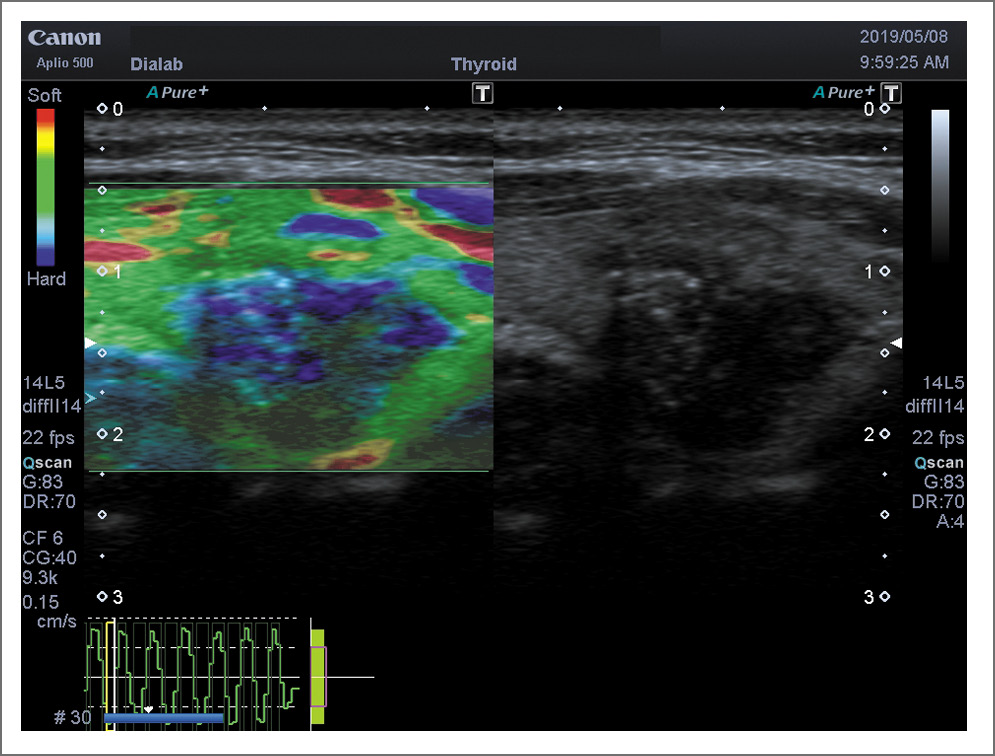

Рис. 4. ПР на фоне АИТ. Компрессионная эластография, по системе Tsukuba–Ueno 5-й тип (характерно для жестких тканей).